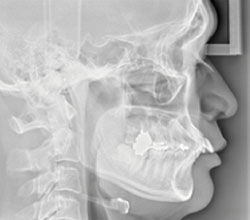

広範囲の撮影が可能なCT(3D撮影)機器です。3D撮影によって多角的な診断が実現し、親知らずの抜歯やインプラント治療、根管治療などの複雑な治療を安全・正確に行うことができます。デジタル方式を採用しているため低被ばくで、被ばく量は従来の機器と比べて大幅に減少しています。

セファロ(側面)